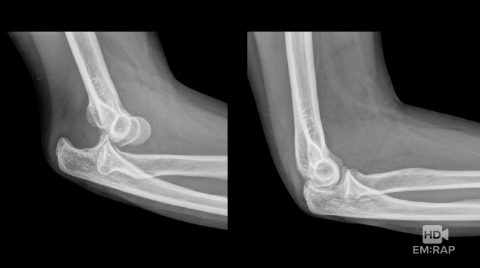

Reduction of Elbow Dislocation

A technique for elbow reduction is demonstrated by Dr. Sukhjit Dhillon.